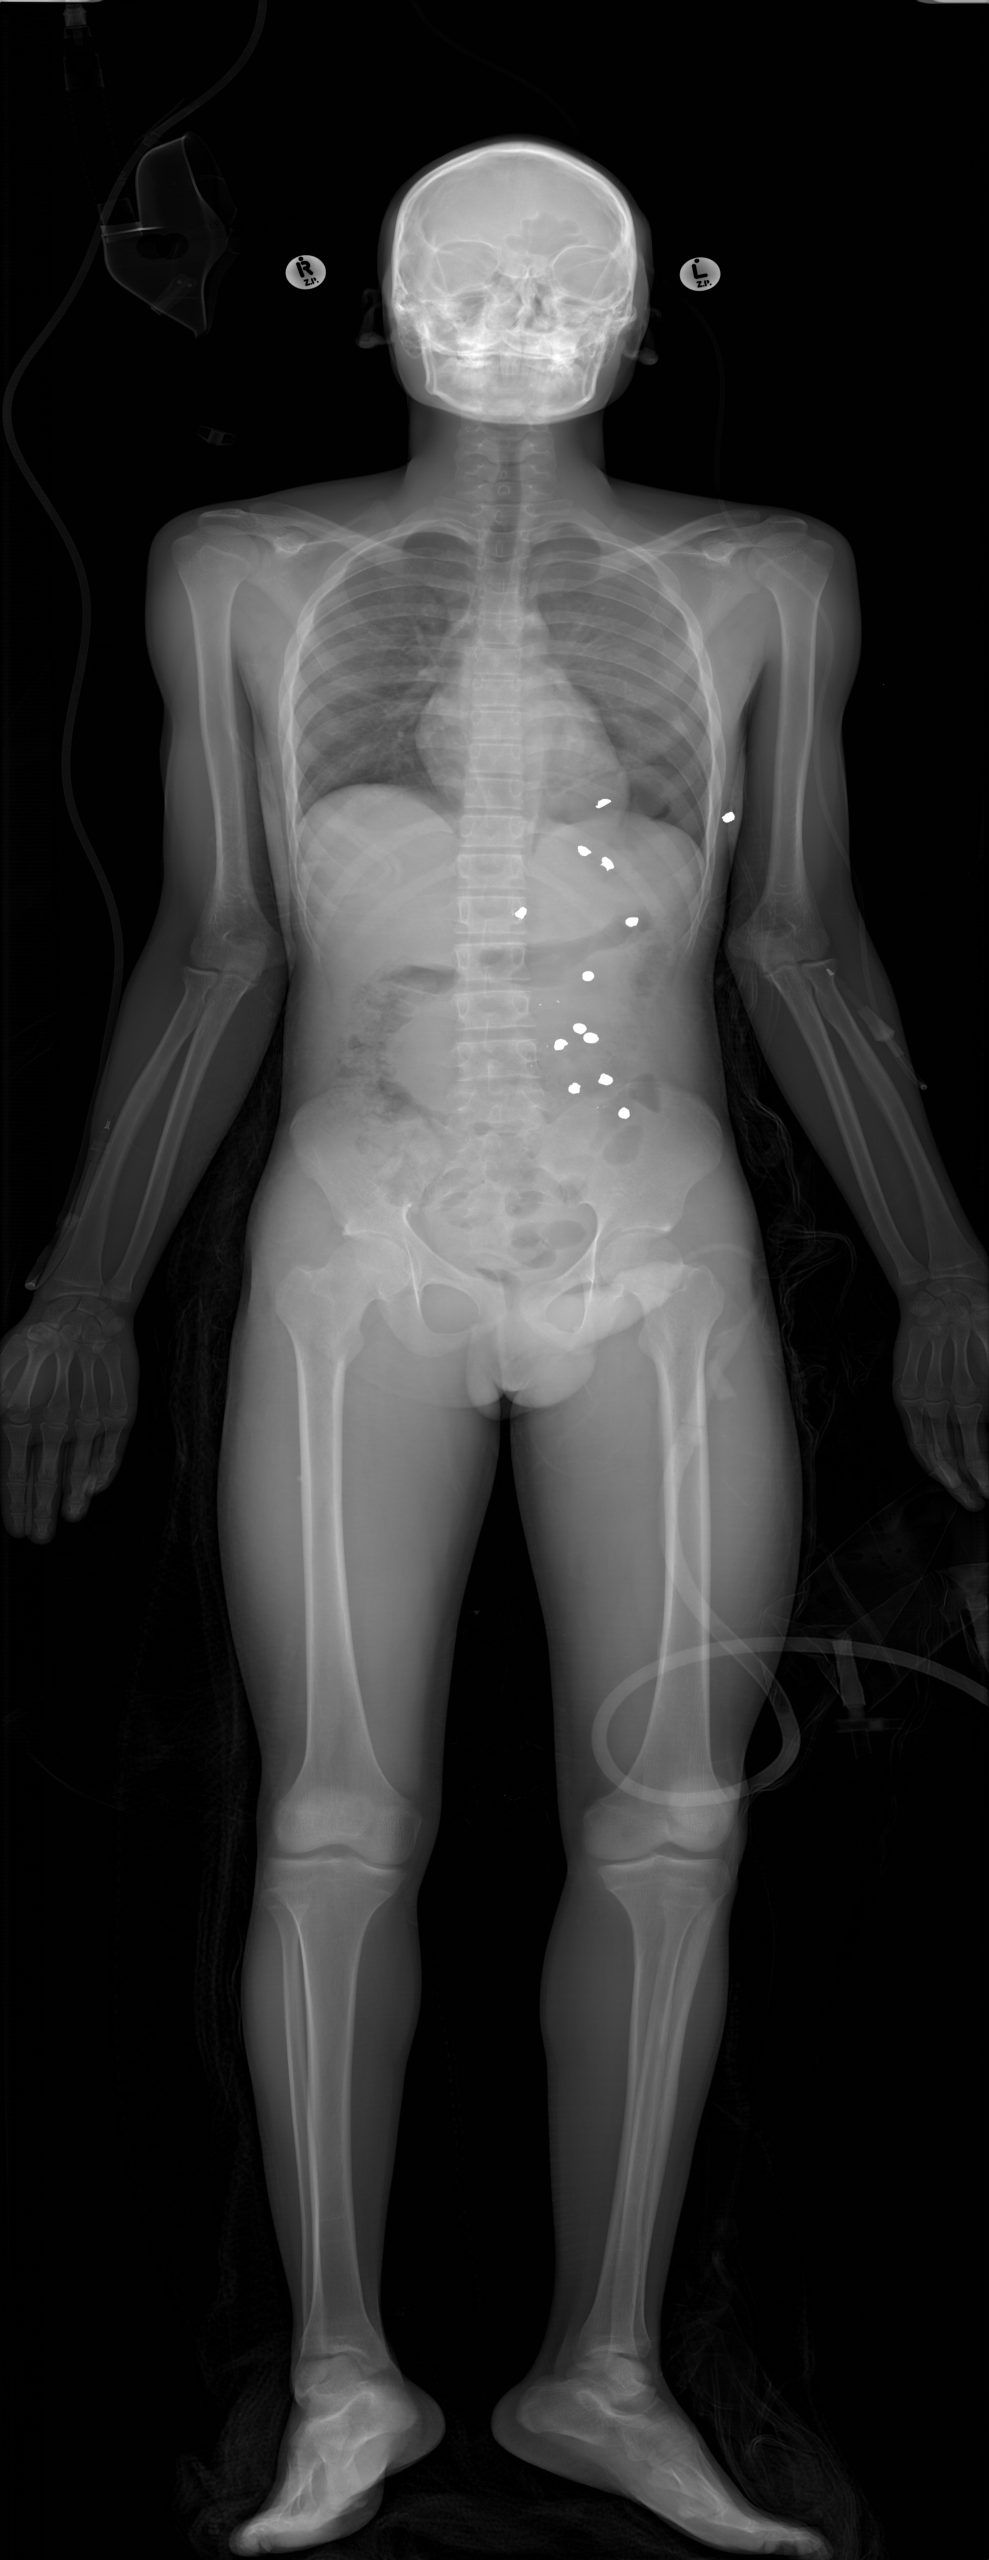

Klinik Görüntüler

Yukarıdaki örnek görüntüler, Lodox Xmplar-dr sisteminin her yaş ve vücut tipindeki hastalarda sunduğu yüksek çözünürlüklü tam vücut görüntüleme kapasitesini göstermektedir. Pediatrik hastalardan erişkinlere, düşük kilolu bireylerden yüksek vücut kitle indeksine sahip hastalara kadar geniş bir hasta grubunda net anatomik detay elde edilebilmektedir. Linear slot-scanning teknolojisi sayesinde kemik, yumuşak doku ve yabancı cisimler tek çekimde, ortalama 13–16 saniyede ve ultra düşük radyasyon dozu ile görüntülenir. Bu özellik, özellikle travma ve acil servis koşullarında hem hızlı tanı koymayı hem de radyasyona bağlı riskleri en aza indirmeyi mümkün kılar.

Lodox Xmplar-dr, çekilen görüntüler üzerinde otomatik ölçüm ve etiketleme özelliği sunarak travma vakalarında kritik bilgilerin hızlıca belirlenmesini sağlar. Sistem, kırık hattı, yabancı cisim, mermi çekirdeği gibi önemli bulguları yüksek hassasiyetle tespit eder ve bunları görüntü üzerinde işaretler. Bu sayede radyologlar ve cerrahlar, tanıya daha kısa sürede ulaşabilir ve tedavi planını hızla oluşturabilir. Klinik veriler, otomatik ölçüm ve etiketleme teknolojilerinin travma hastalarında tanı süresini ortalama %35 kısalttığını ortaya koymaktadır*.